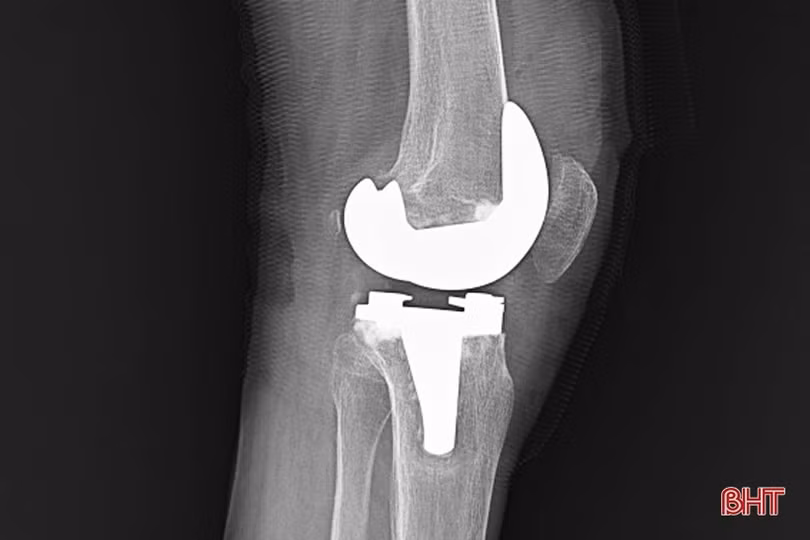

Hình ảnh khớp gối của một bệnh nhân sau phẫu thuật thay khớp.

Bệnh nhân C.V.B (huyện Đức Thọ) không may bị tại nạn chấn thương ở gối được chỉ định phẫu thuật thay khớp gối cho biết: “Tôi phẫu thuật được gần 1 tuần. Hiện nay, phần gối không còn đau nữa và có thể cử động. Dự kiến khoảng vài ngày nữa sẽ ra viện về nhà điều trị phục hồi chức năng”.